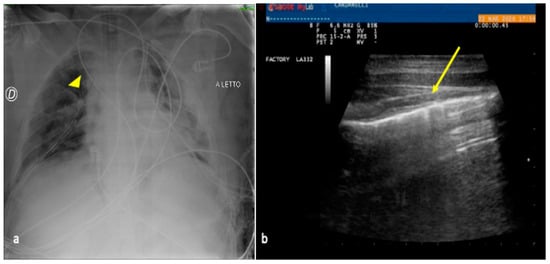

3. Confirming or Excluding Pneumothorax and Monitoring its Evolution